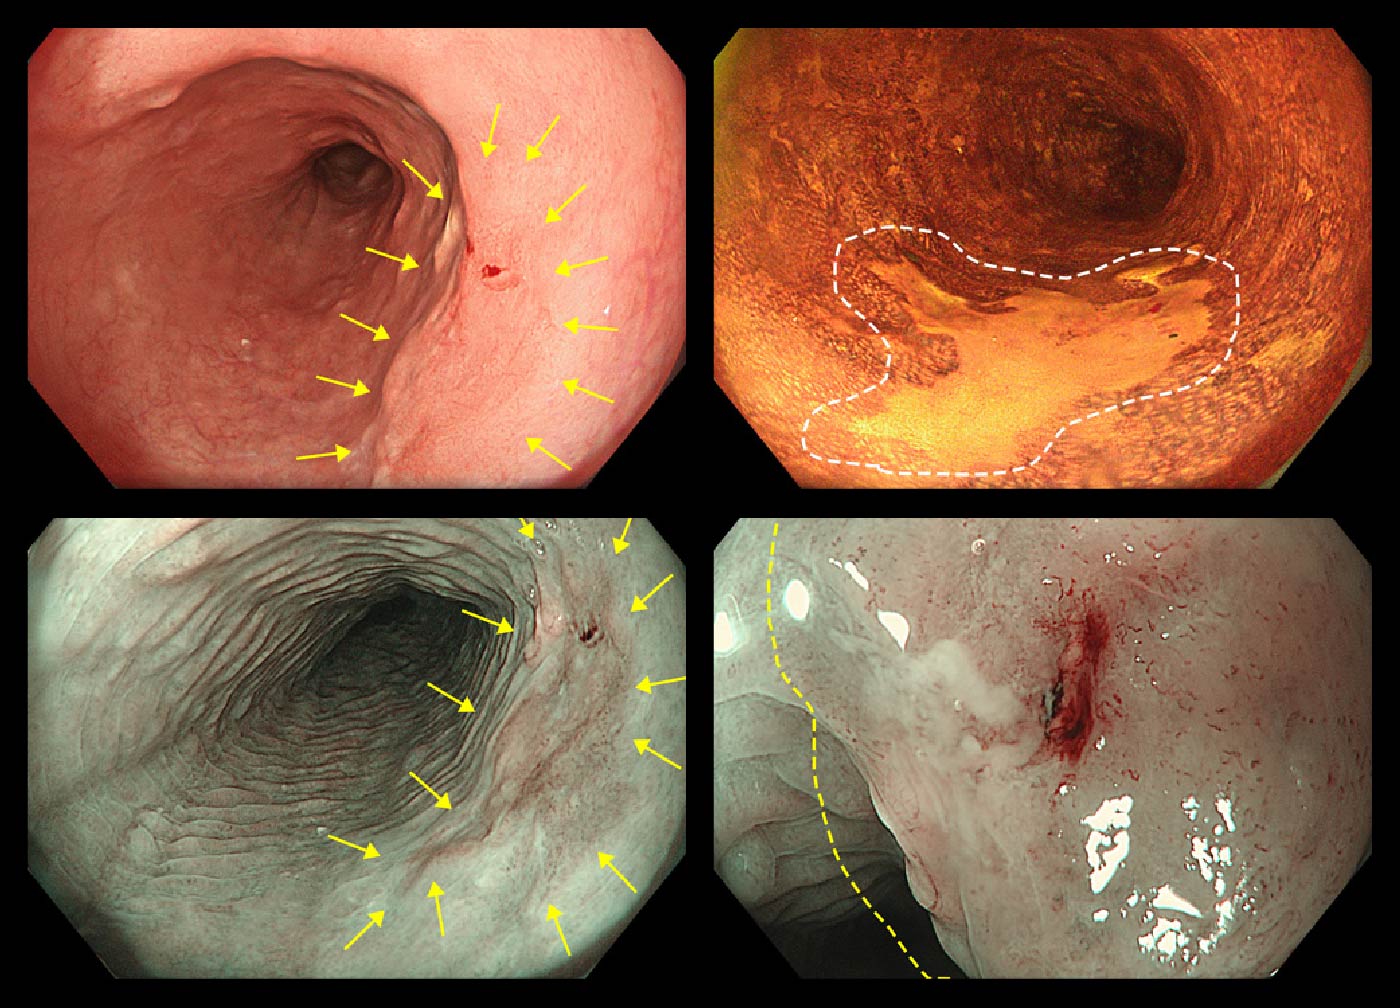

症例①

早期食道がん

左上:TXI-mode2/右上:ルゴール散布

左下:NBI 非拡大/右下:NBI 拡大